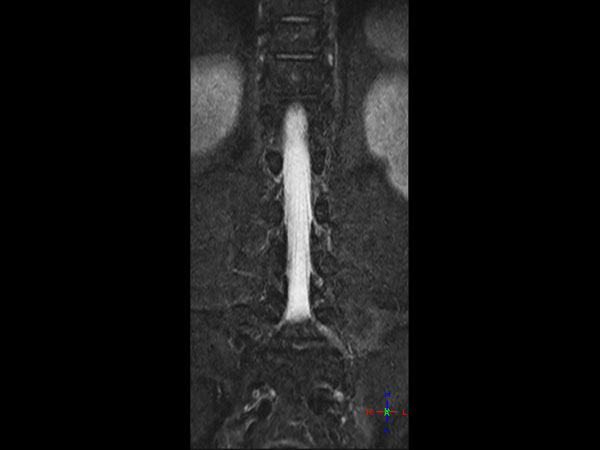

Lumbar Spine - Obese patient

32- year old male patient, 180 kg, with back pain. Was first examined on CT but quality was not sufficient for diagnosis. MRI gave excellent images. Diagnosis: small protrusion of the disc L5/S1, no meningioma.